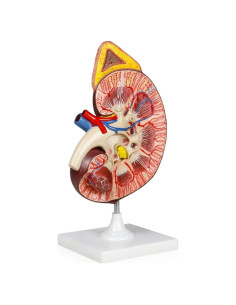

Salud y Equipamiento Médico

Equipamiento Médico

Cuidado de la Salud